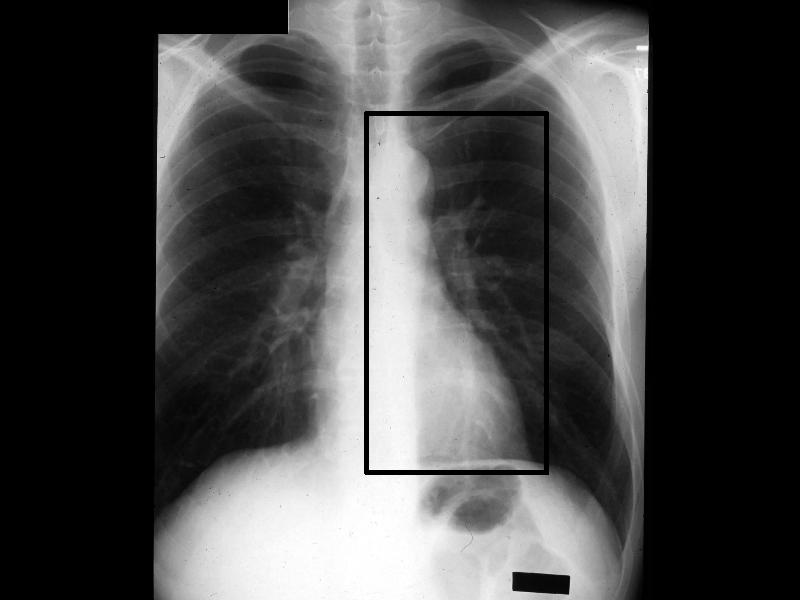

MS 202 CXR NL PA